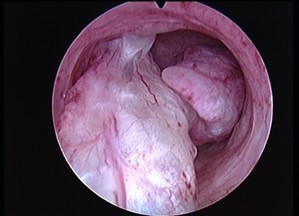

Vous réalisez une hystéroscopie, qui retrouve ceci :

La lésion intracavitaire est irrégulière, vascularisée ; un cancer de l’endomètre est à évoquer en priorité

Le fibrome sous-séreux est par définition visible à l’extérieur de la cavité, au cours d’une cœlioscopie par exemple

L’hyperplasie endométriale se présente de façon plus diffuse

L’anatomopathologiste conclut à un adénocarcinome endométrioïde utérin de grade 1.